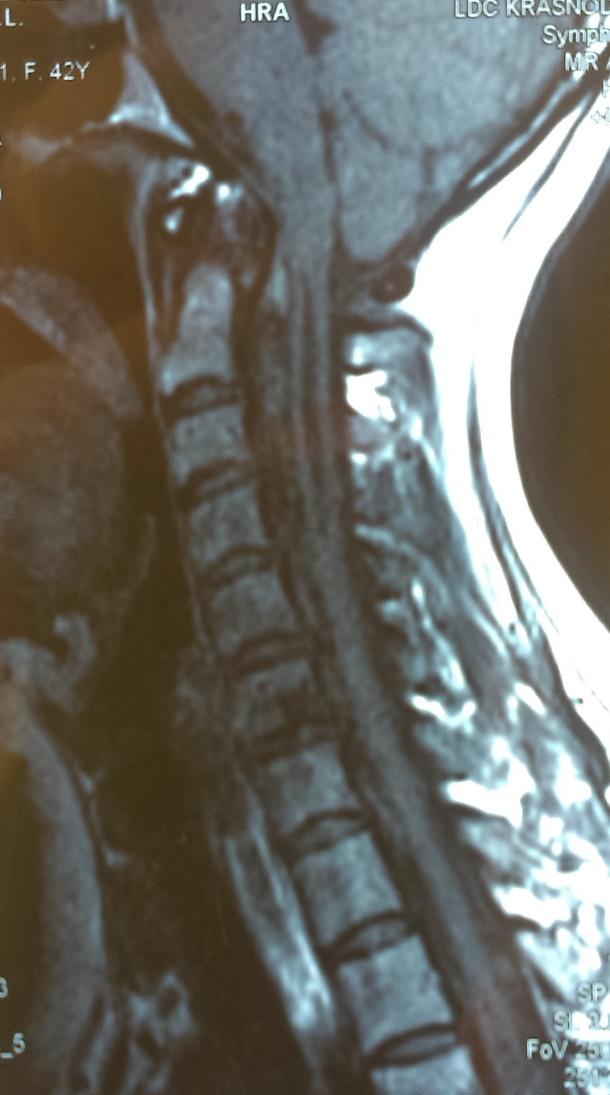

Аномалия Арнольда-Киари: MRI снимки